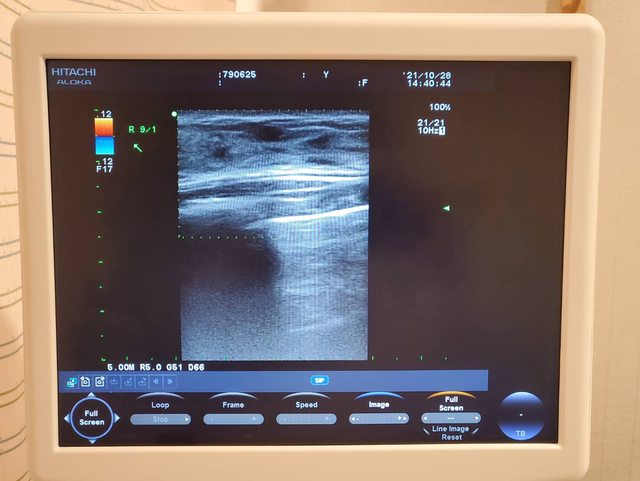

就立即幫我安排做乳房的超音波檢查

超音波室中乾淨隱密 病患可以放心

因為超音波範圍不大 所以使用的探頭較小

透過儀器的檢查發現在右側乳房有一個纖維囊腫

雖然不是看得很明白 但是跟左邊胸部的超音波畫面比起來確實多了東西